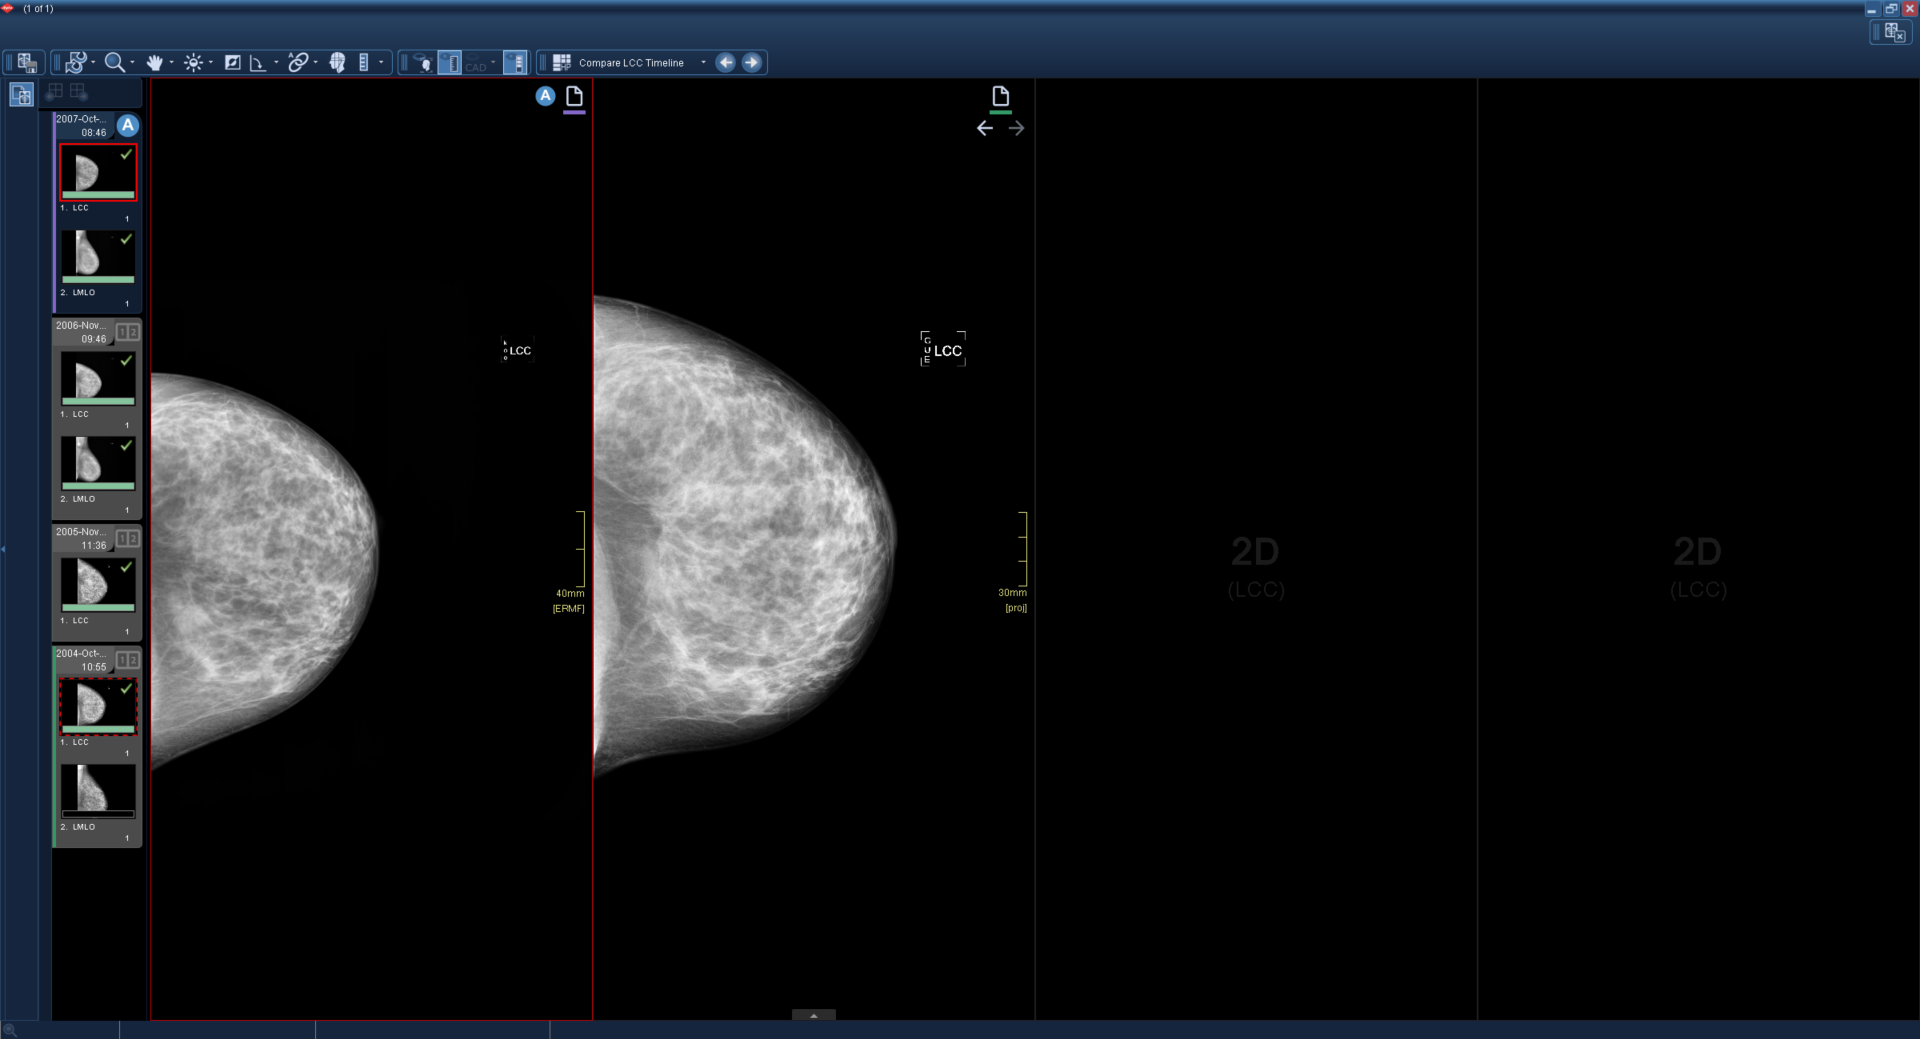

Μια ενεργή εξέταση με τρεις συγκριτικές εξετάσεις φορτώνεται και εμφανίζεται χρησιμοποιώντας το πρωτόκολλο ανάρτησης Compare LCC Timeline.

Χρησιμοποιώντας τη συντόμευση επόμενης συγκριτικής εξέτασης, όλα τα παράθυρα μετακινούνται στην επόμενη συγκριτική εξέταση. Όταν δεν υπάρχουν διαθέσιμες περαιτέρω συγκριτικές εξετάσεις, το παράθυρο είναι μαύρο.

Χρησιμοποιώντας ξανά τη συντόμευση επόμενης συγκριτικής εξέτασης, η τελευταία συγκριτική εξέταση μετακινείται δίπλα στο ενεργό παράθυρο. Όλα τα άλλα παράθυρα σύγκρισης παραμένουν μαύρα.

Η έγχρωμη γραμμή κάτω από το εικονίδιο εξέτασης παραμένει συγχρονισμένη με την πλαϊνή γραμμή κλινικών στοιχείων.